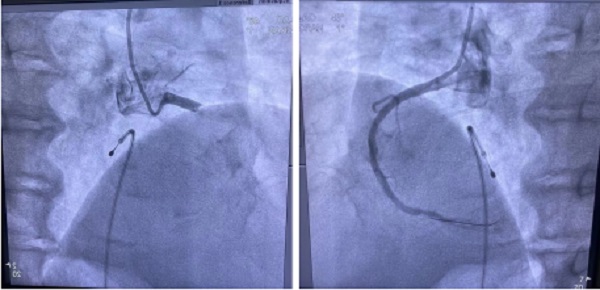

整個的搶救過程驚心動魄:62歲男性患者,因“胸痛2小時”呼叫“120”,救護車上隨車醫(yī)生進行心電圖檢查后立即電話聯(lián)系心內科醫(yī)生劉波,考慮為急性下壁、后壁、右室心肌梗死,竇性停搏,需立刻手術?;颊哌M入導管室時,意識淡漠,全身濕冷,血壓40/20mmHg,心率38次/分,竇性停搏,已處到休克狀態(tài)。手術團隊立即進行介入手術,從穿刺到臨時起搏器置入2分鐘完成,將起搏心室設置為70次/分。手術過程中,造影顯示右冠狀動脈近段完全閉塞,血栓負荷較重,手術團隊立即為其進行冠脈內溶栓、血栓抽吸,冠狀動脈內血流恢復,但患者出現(xiàn)血栓風暴,右冠狀動脈再次閉塞,再次恢復血流,患者出現(xiàn)室顫,立即進行電除顫,患者重新恢復心律。生死線上轉了幾圈,最終救治成功!